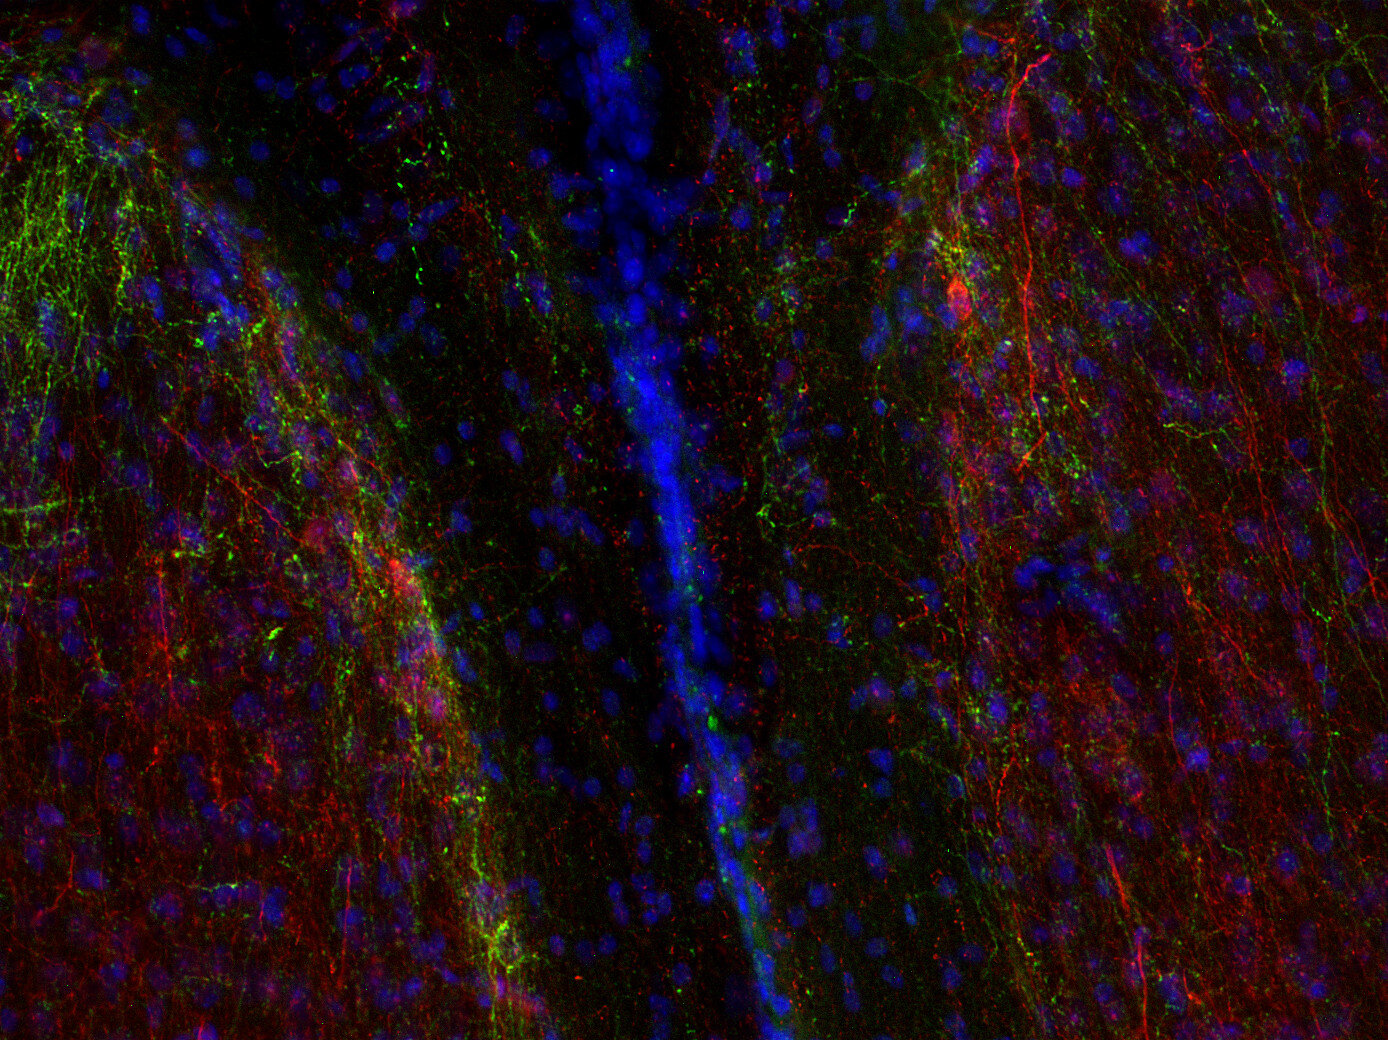

DOPA decarboxylase antibody - 369 004

IHC: 1 : 500 gallery

Immunohistochemistry (IHC) on 4% PFA perfusion fixed tissue with 24h PFA post fixation. Immunoreactivity is usually revealed by fluorescence or a chromogenic substrate. Some antibodies require special fixation methods or antigen retrieval steps. For details, please refer to the ”Remarks” section.

Specificity DOPA decarboxylase

DOPA decarboxylase, also referred to as aromatic L-amino acid decarboxylase, AADC or DDC, is the second enzyme in the biosynthesis of dopamine and serotonin. In addition, it is responsible for the synthesis of the trace amines phenylethylamine, p-tyramine, and tryptamine, which are considered to act as neuromodulators.

DDC is expressed in the central nervous system, but has also been detected in several tissues such as liver, kidney, small intestine, adrenal gland and blood vessels.